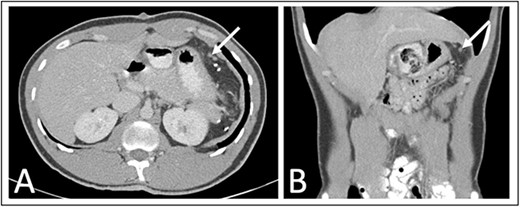

He was seen at 1, 6, and 12 months following surgery without complaints. A 1-year interval abdominal CT (Fig. 3) showed several 3–6 mm nodules in the left upper quadrant near the splenectomy site with the differential including several small lymph nodes, tiny splenules, or neoplastic implants that will be followed with another 1-year interval CT scan.

One year post operative abdominal CT scan (A) axial and (B) coronal abdominal CT images showing several sub-centimeter nodules in the post-splenectomy bed (arrows).